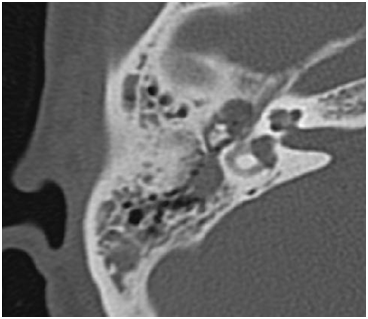

The patient was M.E.M., 50years old, ASA1, female with chronic ear disease with polyposis of the right ear; with moderate type I (50dB HL) conductive hearing loss. A CT scan is presented on Figure 1 & 2. The treatment was initiated after written informed consent, with amoxicillin and clavulanic acid (875 m+ 125 mg) in a form of ½ pill twice per day and prednisolone 5mg /day.

Figure 1 MEM, 50 yrs female, OMC with polyps, R ear before treatment.

Figure 2 MEM, 50 yrs female, OMC wit polyps, R ear before treatment.